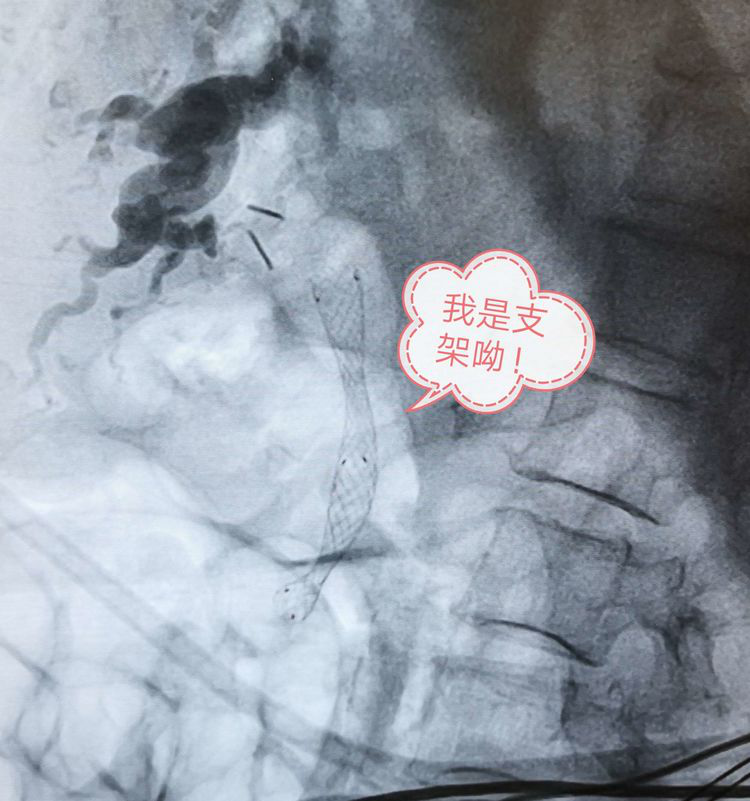

順利置入金屬膽道支架。

支架置入后,立刻見到膽汁涌出。